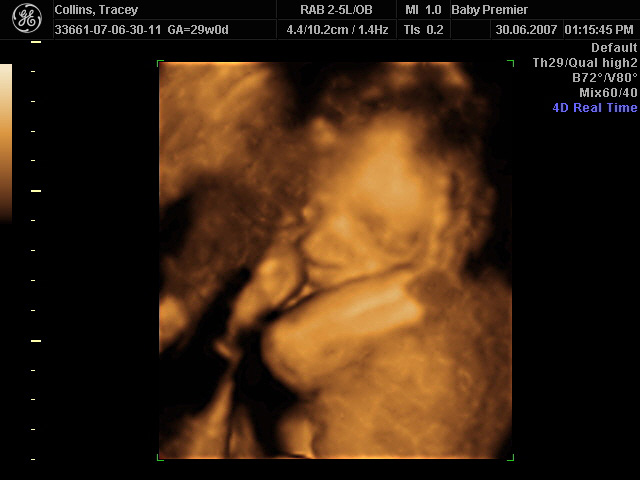

On 30th June 2007, we had a scan of our baby done in "4D" - fancy speak for a moving 3D image.

So far, so 3D... Time to add the 4th dimension!